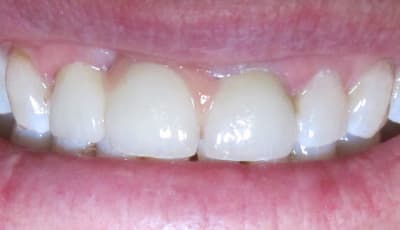

L'état paro du bas est super moche.

La 21 aurait du être allongée apicalement, elle est moins longue que la 12...

le problème ici sont les embrasures effectivement.

2 les dents sont assez peu hautes, on pourrait en profiter pour faire des élongations coronaires sur les incisives.

Ces 2 éléments conjugués auraient peut etre pu supprimer la ceram rose...

je préfère un allongement coronaire de 2mm sur la 21 à 2mm de céramique rose sur la 11